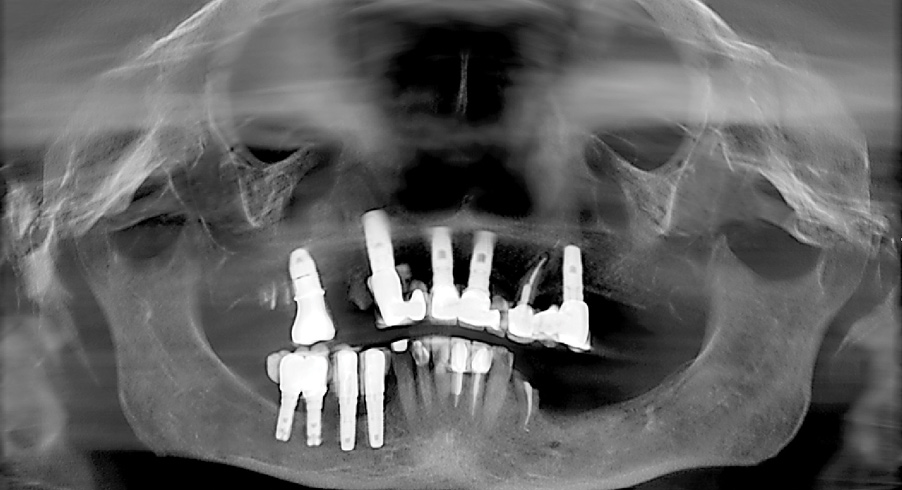

Removal of Dental Implants

All-on-4–style treatment sometimes requires the removal of previously placed dental implants (Figure 16 and Figure 17). Although some of these implants may have biologic complications such as peri-implantitis that may ease the removal process, most previously placed implants requiring explantation by the author have been firmly osseointegrated. Previously placed dental implants are not typically suitable for All-on-4–style surgeries because the platforms were placed to a level in accordance with the natural teeth. Although this is perfectly suitable when natural teeth are present, these platform positions are too coronal for All-on-4–style treatment. Furthermore, previously placed dental implants preclude the ability for adequate bone reduction. In the author’s experience, using previously placed dental implants for All-on-4–style treatment often results in restorations of inadequate thickness that have a propensity for fracture due to the coronal position of the platforms and the lack of bone reduction. As such, the author routinely removes previously placed dental implants when performing All-on-4–style treatment.

Dental implant removal for All-on-4–style surgery is particularly concerning because of the need for immediately loading a prosthesis. Dental implants requiring removal are typically the same diameter as the implants intended for use in the All-on-4–style surgery. If the implants can be removed with a high-torque dental implant retrieval tool (Figure 18), bone is preserved and a dental implant of at least the same diameter and length can be used for the All-on-4–style treatment. Should the implant retrieval tool fail to explant the previously placed dental implant, trephination is required. The bone loss subsequent to trephination of a dental implant may eliminate the possibility of placing a new implant and thus compromise immediate loading of a transitional prosthesis. As has been reported by others,43-45 the author has had a high degree of success in removing previously placed dental implants with high-torque retrieval tools. In cases in which trephination was required, the author has replaced the previously existing implants with new implants of both wider and longer dimensions.

Fig 16. Presurgical panoramic radiograph of a patient receiving All-on-4–style treatment with multiple dental implants requiring explantation. Note the dental implants in the mandibular right quadrant that are compromising the inferior alveolar nerve.

Figure 16

Fig 17. Postsurgical panoramic radiograph of the patient from Figure 16 following All-on-4–style dental implant treatment.

Figure 17